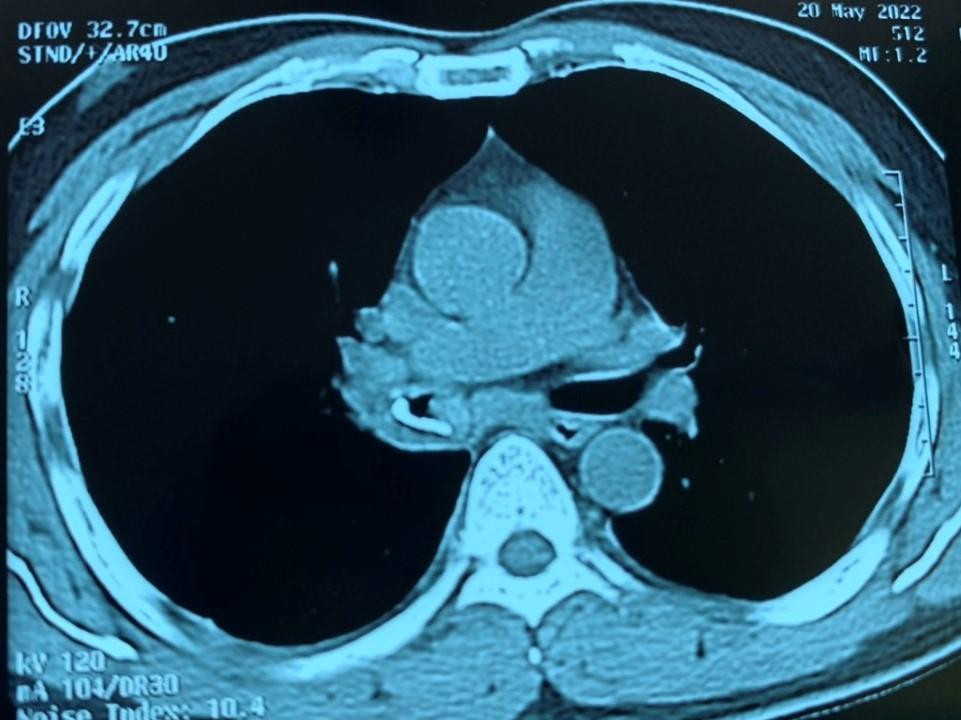

| Kết quả kiểm tra hình ảnh ghi nhận dị vật nằm ở phế quản của người bệnh |

Tuy nhiên, gần đây tình trạng ho ra máu ngày càng trầm trọng hơn, bệnh nhân đến một bệnh viện tại TPHCM thăm khám, được bác sĩ chỉ định chụp phim phổi. Hình ảnh kiểm tra cho thấy bệnh nhân có tình trạng viêm phổi, hậu tắc nghẽn. Kết quả CT phát hiện người bệnh có dị vật ở phế quản. Bệnh nhân được nội soi gắp dị vật 2 lần nhưng không thành công nên được chuyển đến Bệnh viện Chợ Rẫy.

BS Phạm Thị Vân Thanh cho biết, vị trí mảnh xương nằm khuất sau bóng tim là nguyên nhân 20 năm qua bác sĩ không thể nhìn thấy dị vật trên phim X-quang. Mảnh xương sắc nhọn, cắm sâu vào thành phế quản suốt 20 năm đã mọc rất nhiều mô hạt nên việc nội soi gắp dị vật rất khó khăn.